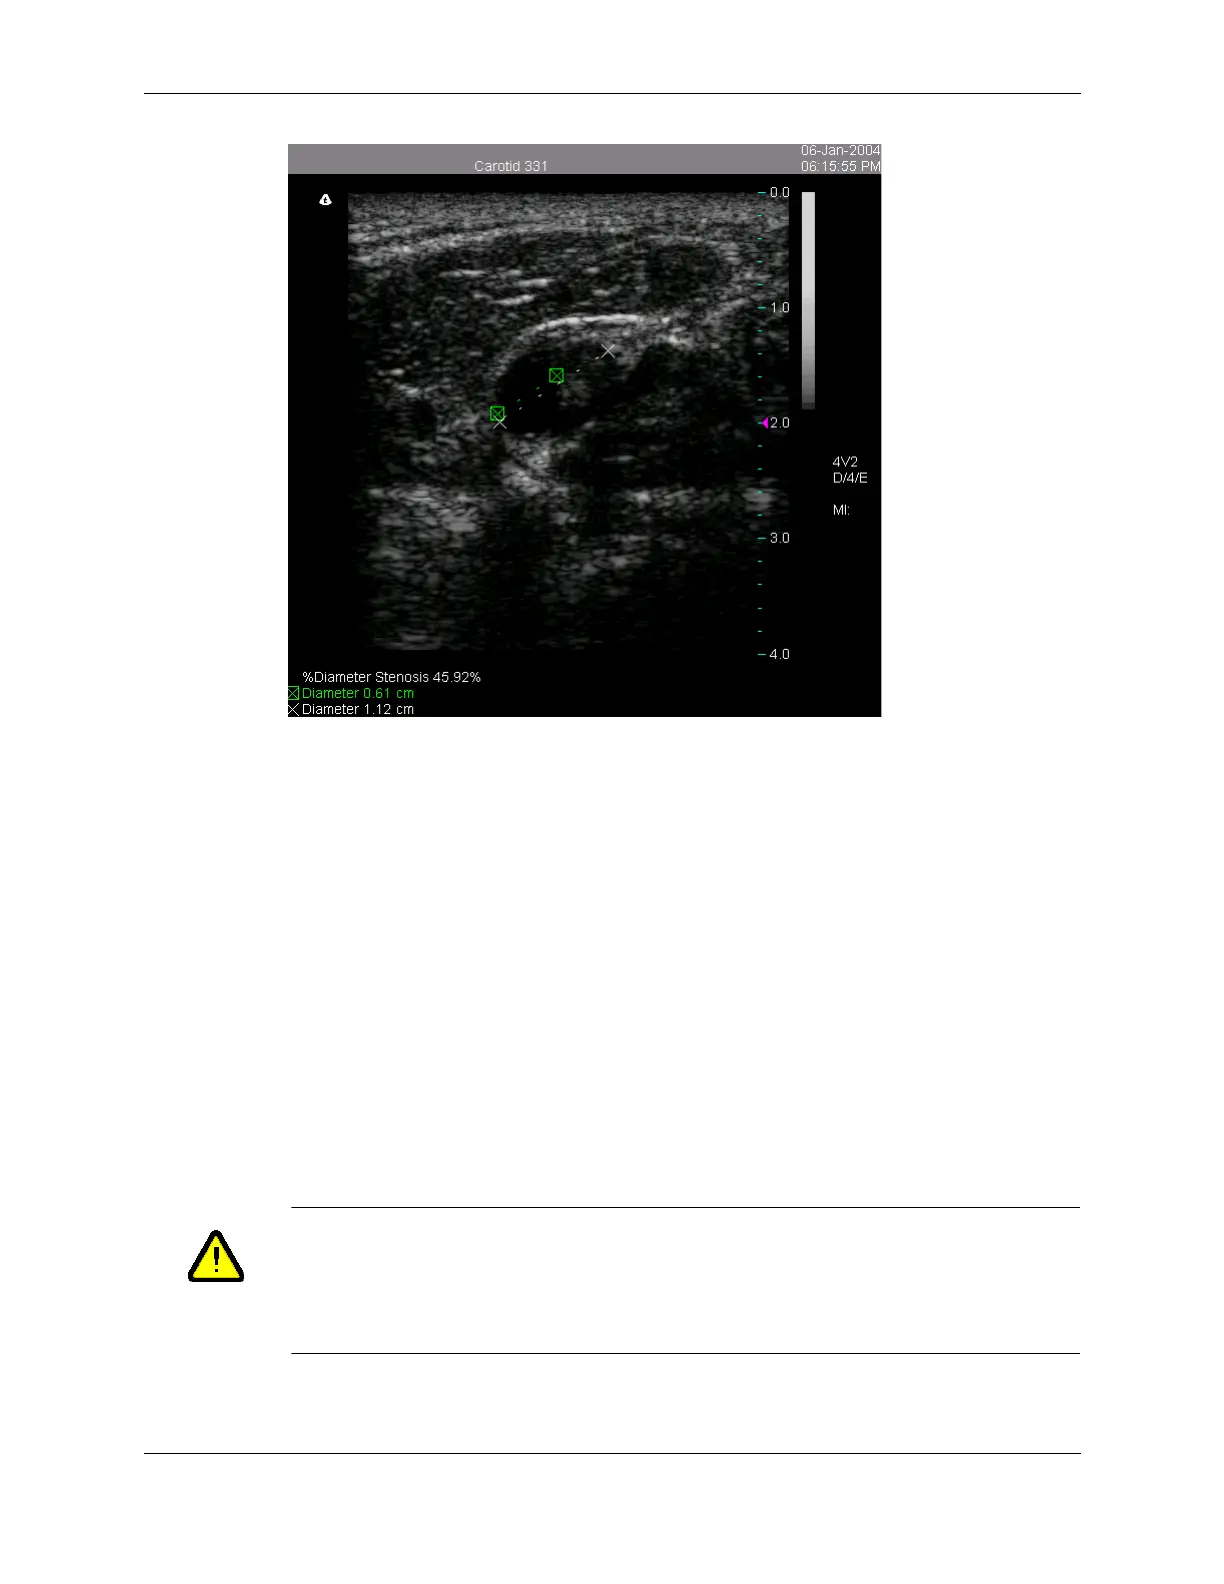

Calculated % Diameter Stenosis

You can use the same procedure to calculate the % Area Stenosis. Select Stenosis Area

from the measurement menu and use the Trace tool to measure the vessel and the residual

lumen.